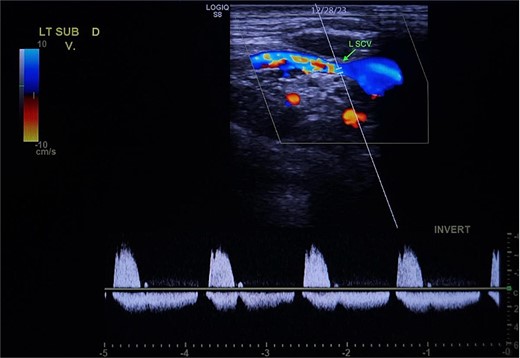

A 67-year-old male with a medical history significant for hypertension, diabetes, coronary artery disease, carotid artery stenosis, osteoarthritis, and 50 pack-year smoking history presented initially to an orthopedic surgery office for evaluation of left shoulder pain after exercising. The patient was found to have an underlying rotator cuff injury and was subsequently treated with cortisone injection. The patient subsequently developed septic arthritis, ultimately requiring incision and drainage of the abscess and resection of the sternoclavicular joint, partial first rib, and partial clavicle. The patient required multiple washouts and debridement procedures, ultimately leading to septic shock and bacteremia requiring close observation in the surgical intensive care unit. A computed tomography angiogram (CTA) of chest was performed at the time and revealed a subcentimeter penetrating ulcer, arising from the proximal left subclavian artery likely secondary to surgical trauma, which was observed nonoperatively given the patient critical status in the intensive care unit (ICU) (Figs 1 and 2). During the ICU course, the patient developed left upper extremity swelling A left upper extremity duplex ultrasound subsequently revealed a nonocclusive deep vein thrombosis of the subclavian vein and also showed resolution of a pseudoaneurysm (PSA) of the subclavian artery. The patient was started on anticoagulation at this time for a deep vein thrombosis (DVT). The patient was ultimately discharged upon resolution of his acute infection to a rehabilitation facility. During the third-month follow-up office visit, the fistulous connection between the subclavian artery and vein was found incidentally on left upper extremity duplex ultrasound (Fig. 3). Physical exam of the patient was otherwise unremarkable with palpable upper extremity pulses and the patient did not appear to have any symptoms related to the fistula including upper extremity swelling or open wounds. The patient was scheduled for an elective repair of the fistula via endovascular stent graft placement. The patient was brought to the operating room, and the radial artery was accessed with a micropuncture device. Radial artery access was our choice to intervene given the location of fistula. When left upper extremity angiography was performed, it revealed a blush of contrast from proximal subclavian artery, revealing a small fistula between subclavian artery and subclavian vein (Fig. 4). Subsequently, a 6 × 29 mm balloon-mounted stent graft was used to cover the fistula. Completion angiography was performed showing adequate seal with resolution of the fistula (Fig. 5). The patient tolerated the procedure well and was subsequently discharged from the hospital the same day. He was started on antiplatelet therapy post-operatively and continued oral anticoagulation for the DVT. The patient was seen in the office at 3-month follow-up, where a repeat duplex ultrasound revealed normal waveforms and velocities throughout the left arm. He was also seen in the office recently, and he is doing well with no new complaints.

Demonstration of arterial waveform in the left subclavian vein on Duplex ultrasound (green arrow: left subclavian vein).